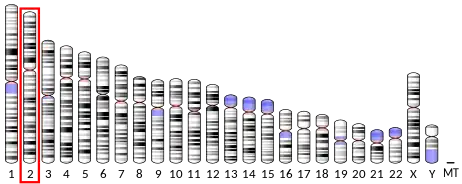

5-Hydroxytryptamine receptor 2B (5-HT2B) also known as serotonin receptor 2B is a protein that in humans is encoded by the HTR2B gene.[5][6] 5-HT2B is a member of the 5-HT2 receptor family that binds the neurotransmitter serotonin (5-hydroxytryptamine, 5-HT). Like all 5-HT2 receptors, the 5-HT2B receptor is Gq/G11-protein coupled, leading to downstream activation of phospholipase C.